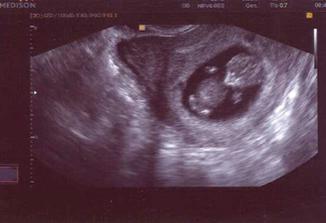

26.8. doufam ze nam ukaze uz i srdicko .-))) no zacala jsem plasit kvuli spineni ale nastesti zbytecne.....videli jsme srdicko ...nase auticko uz ma i moturek huraaa..